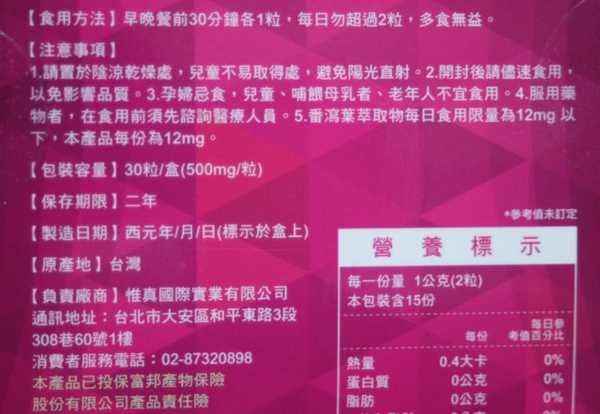

食用方式:早晚餐前30分鐘各1粒,每日不超過2粒。(多食無益)

番瀉葉萃取物每日食用限量為12mg以下,

每一盒Supercut塑魔纖立塑膠囊都有三小包,每一小包有10顆膠囊